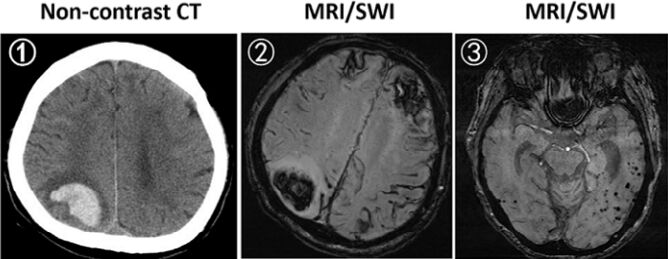

45.82 歲女性病人突然發生右側枕葉頭痛合併左側視野缺損,無顯影劑之腦部電腦斷層(non-contrast CT)檢 查結果如下圖①,磁振造影之磁敏感加權成像(susceptibility weighted imaging, SWI)結果如下圖② ③。下列何者最有可能是此病人的診斷? (A)腫瘤併發腦轉移及腦出血 (B)腦部隱球菌(cryptococcus)感染合併腦出血 (C)大腦類澱粉血管病變(cerebral amyloid angiopathy)合併腦出血 (D)原發性中樞神經系統血管炎(primary angiitis of central nervous system)合併腦出血